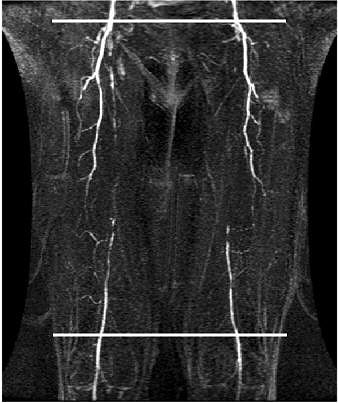

![]() |

| White lines indicate sites of cine phase contrast flow velocity measurements. All images courtesy of Dr. Kiyarash Mohajer. |

In a secondary arm of this study, the group tested induced hyperemia using systolic thigh compression with a blood pressure cuff inflated for three minutes. They measured flow before, during, and after compression. Once again, they found that arterial flow changes across atherosclerotic lesions correlated with stenosis severity, Mohajer said.